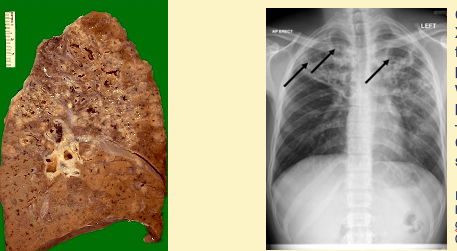

Dr de Silva, a junior doctor, spent 6 months working in a refugee camp in Thailand. She presents to her GP with fatigue, malaise and cough of one month's duration occasionally productive of rust-coloured sputum. Dr de Silva has also noted 3 kg weight loss in the last month. She does not smoke. Her GP arranges for a chest x-ray, image shown on the left. The radiologist phones the GP because she is concerned about the abnormalities shown by the arrows. **Q3a: What is the most likely diagnosis in this patient?** **Q3b: What type of abnormality(s) does the chest x-ray show? Describe in detail**. **Q3c: What are risk factors for the disease Dr de Silva most likely has? – list a minimum of three (they do not have to be specific to Dr de Silva).**

Dr de Silva, a junior doctor, spent 6 months working in a refugee camp in Thailand. She presents to her GP with fatigue, malaise and cough of one month's duration occasionally productive of rust-coloured sputum. Dr de Silva has also noted 3 kg weight loss in the last month. She does not smoke. Her GP arranges for a chest x-ray, image shown on the left. The radiologist phones the GP because she is concerned about the abnormalities shown by the arrows. Q3a: What is the most likely diagnosis in this patient? **Patient’s symptoms and chest x-ray suggest primary TB** Q3b: What type of abnormality(s) does the chest x-ray show? Describe in detail. **Ghon foci – little arrow; primary TB site Enlarged hilar lymph nodes – big arrow – together called a Ghon COMPLEX. Consistent with primary TB (vs reactivation TB)** Q3c: What are risk factors for the disease Dr de Silva most likely has? – list a minimum of three (they do not have to be specific to Dr de Silva). **Recent arrival or travel country where TB endemic Work in areas endemic for TB HIV Poorly controlled Type 2 Diabetes Mellitus Other immunocompromise states (i.e. cancer for which patient undergoing chemotherapy) Homeless Drug users, prison inmates Close contacts of patients with MTB disease**